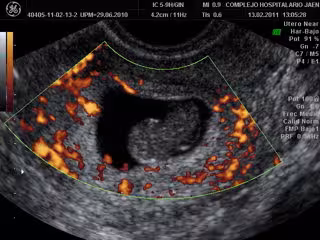

Imagen ecográfica de un aborto espontáneo

A todas ellas se les practicó una ecografía, se les extrajo una muestra sanguínea para realizar determinaciones analíticas y se les pasó un cuestionario. En total, se recogieron 131 variables en cada participante.